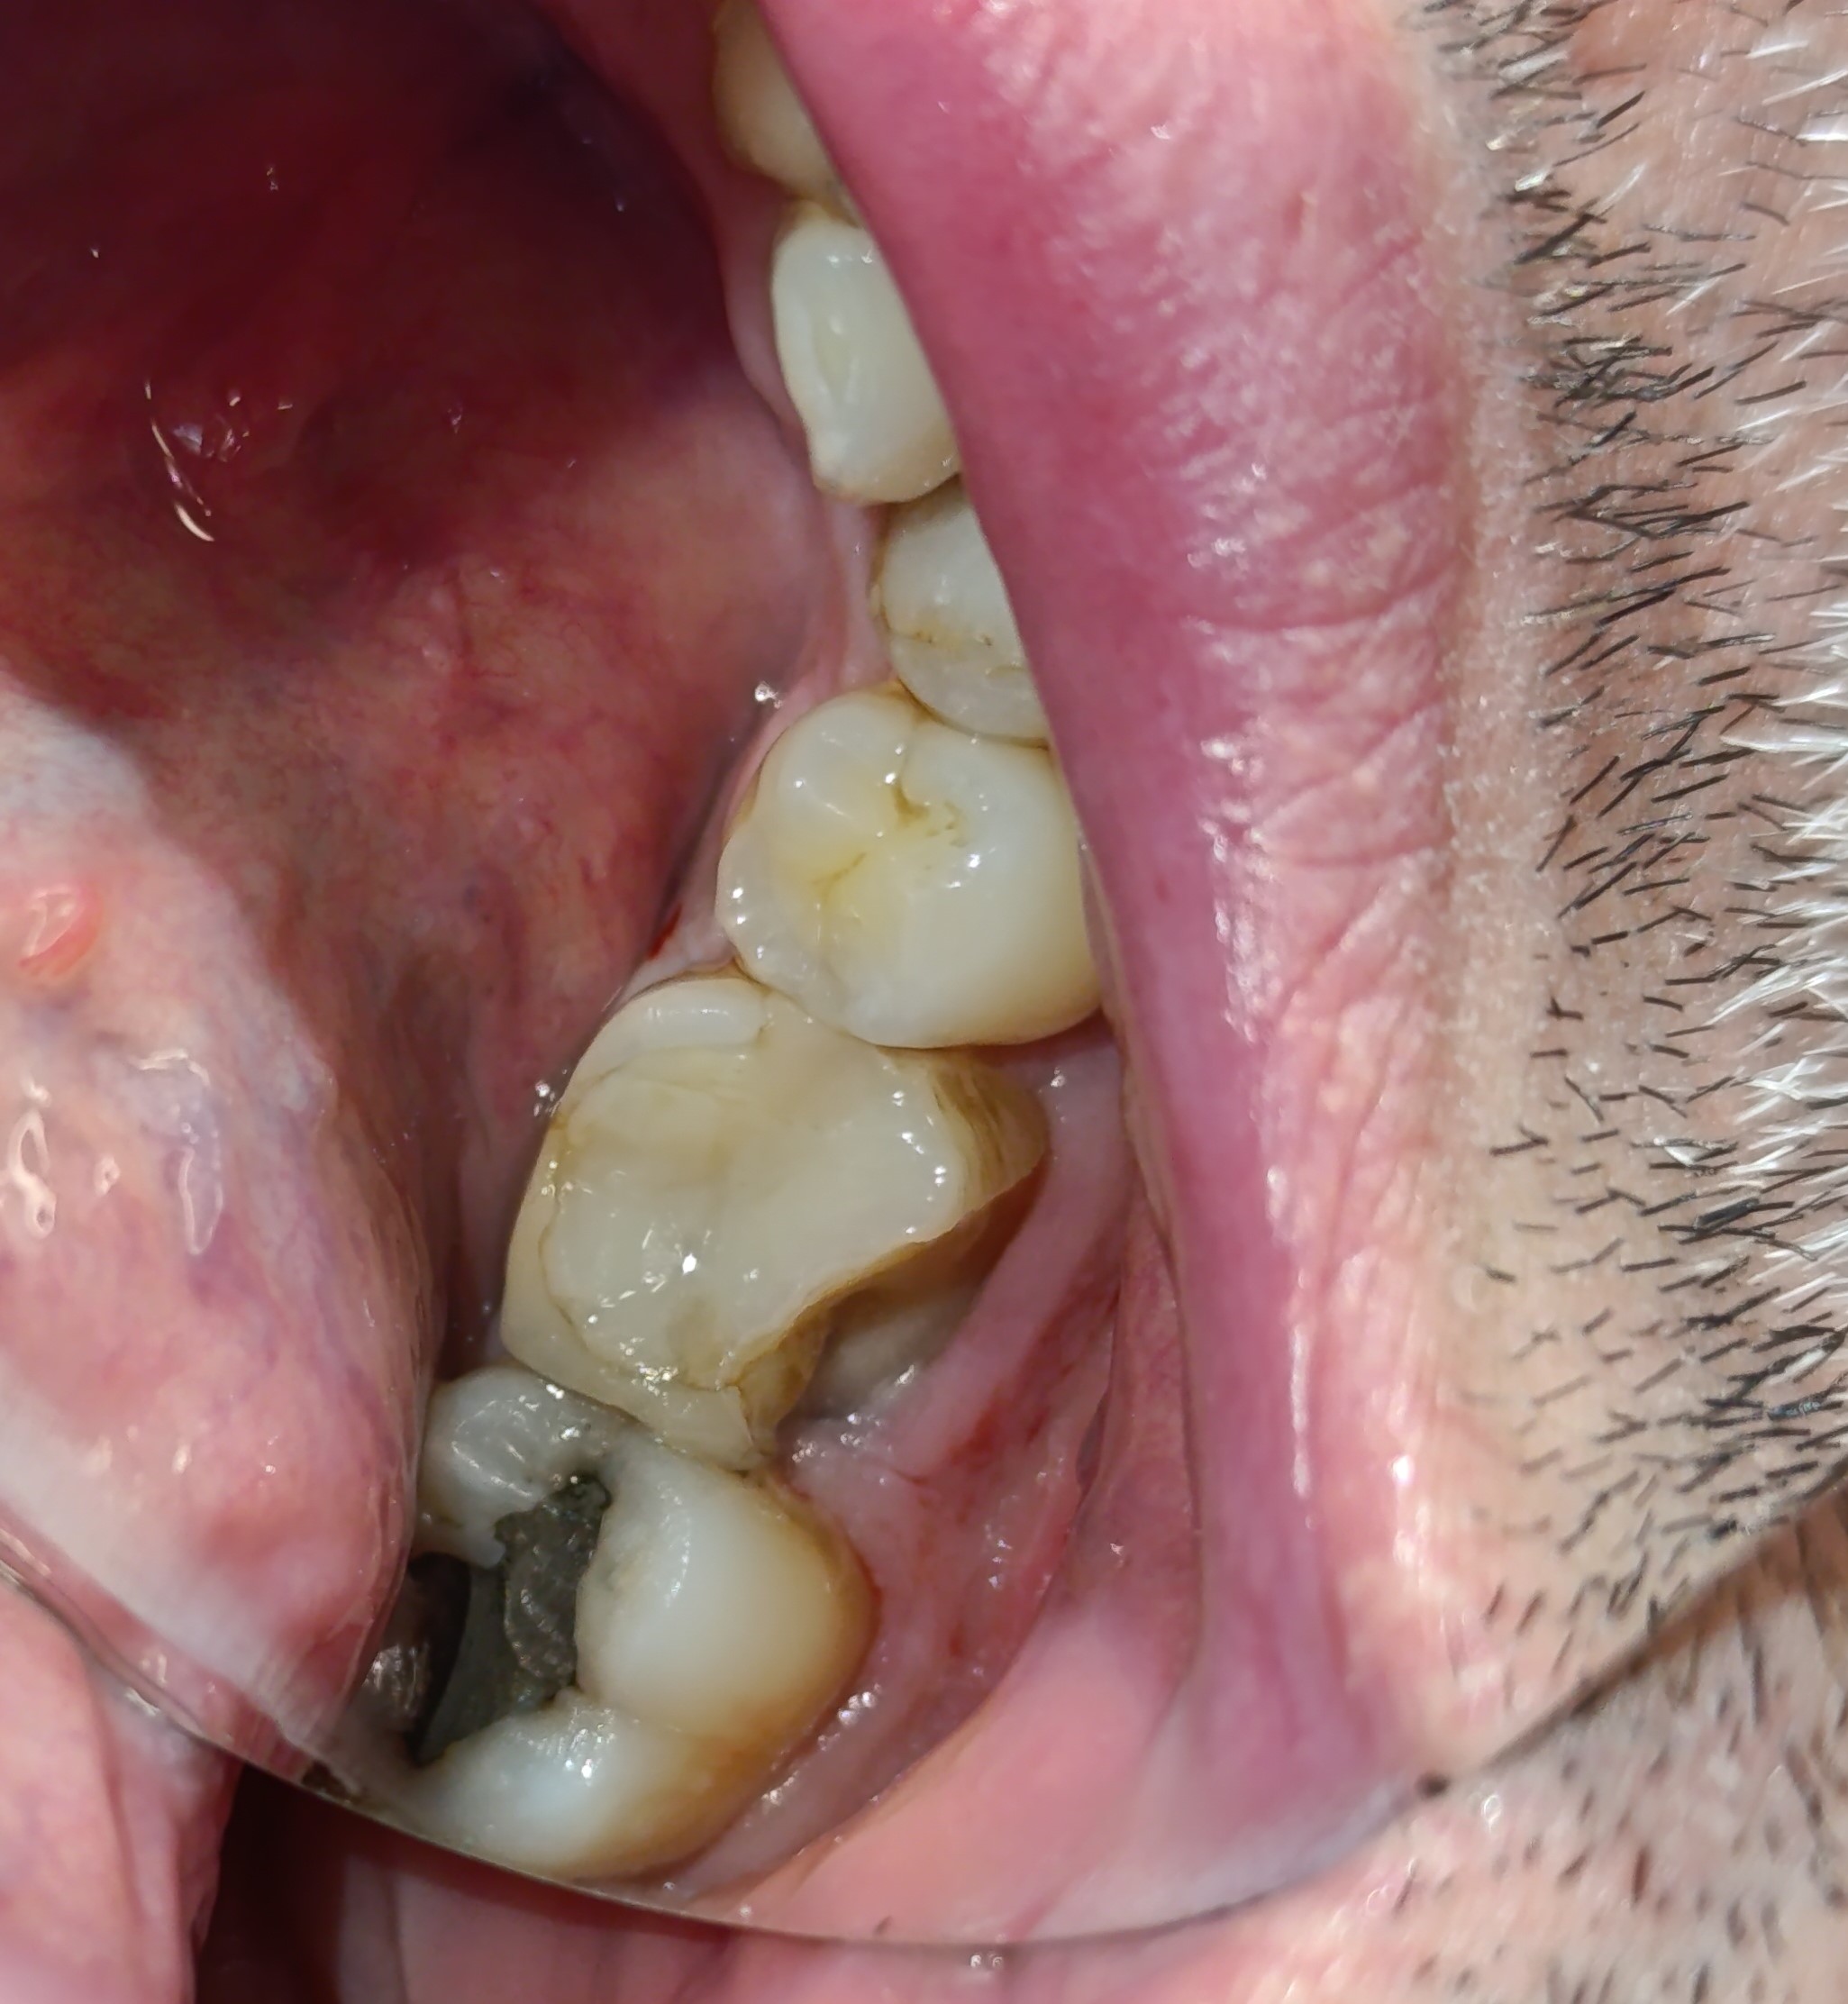

Ο πρώτος γόμφιος στην αριστερή πλευρά της κάτω γνάθου είχε απονευρωθεί στο παρελθόν. Ο ασθενής δεν θέλησε να καλύψει το δόντι με θήκη, ώστε να είναι πλήρως προστατευμένο με αποτέλεσμα το δόντι να σπάσει (όπως φαίνεται στην αρχική εικόνα). Η λύση θεραπείας ήταν η κατασκευή στεφάνης δοντιού, αφού προηγουμένως το δόντι τροχίστηκε καταλλήλως και ο οδοντοτεχνίτης κατασκεύασε την ολοκεραμική θήκη ζιρκονίου.

Το δόντι είναι πλέον πλήρως προστατευμένο και μπορεί να αντέξει στο πέρασμα των χρόνων.

ΠΡΙΝ

ΜΕΤΑ